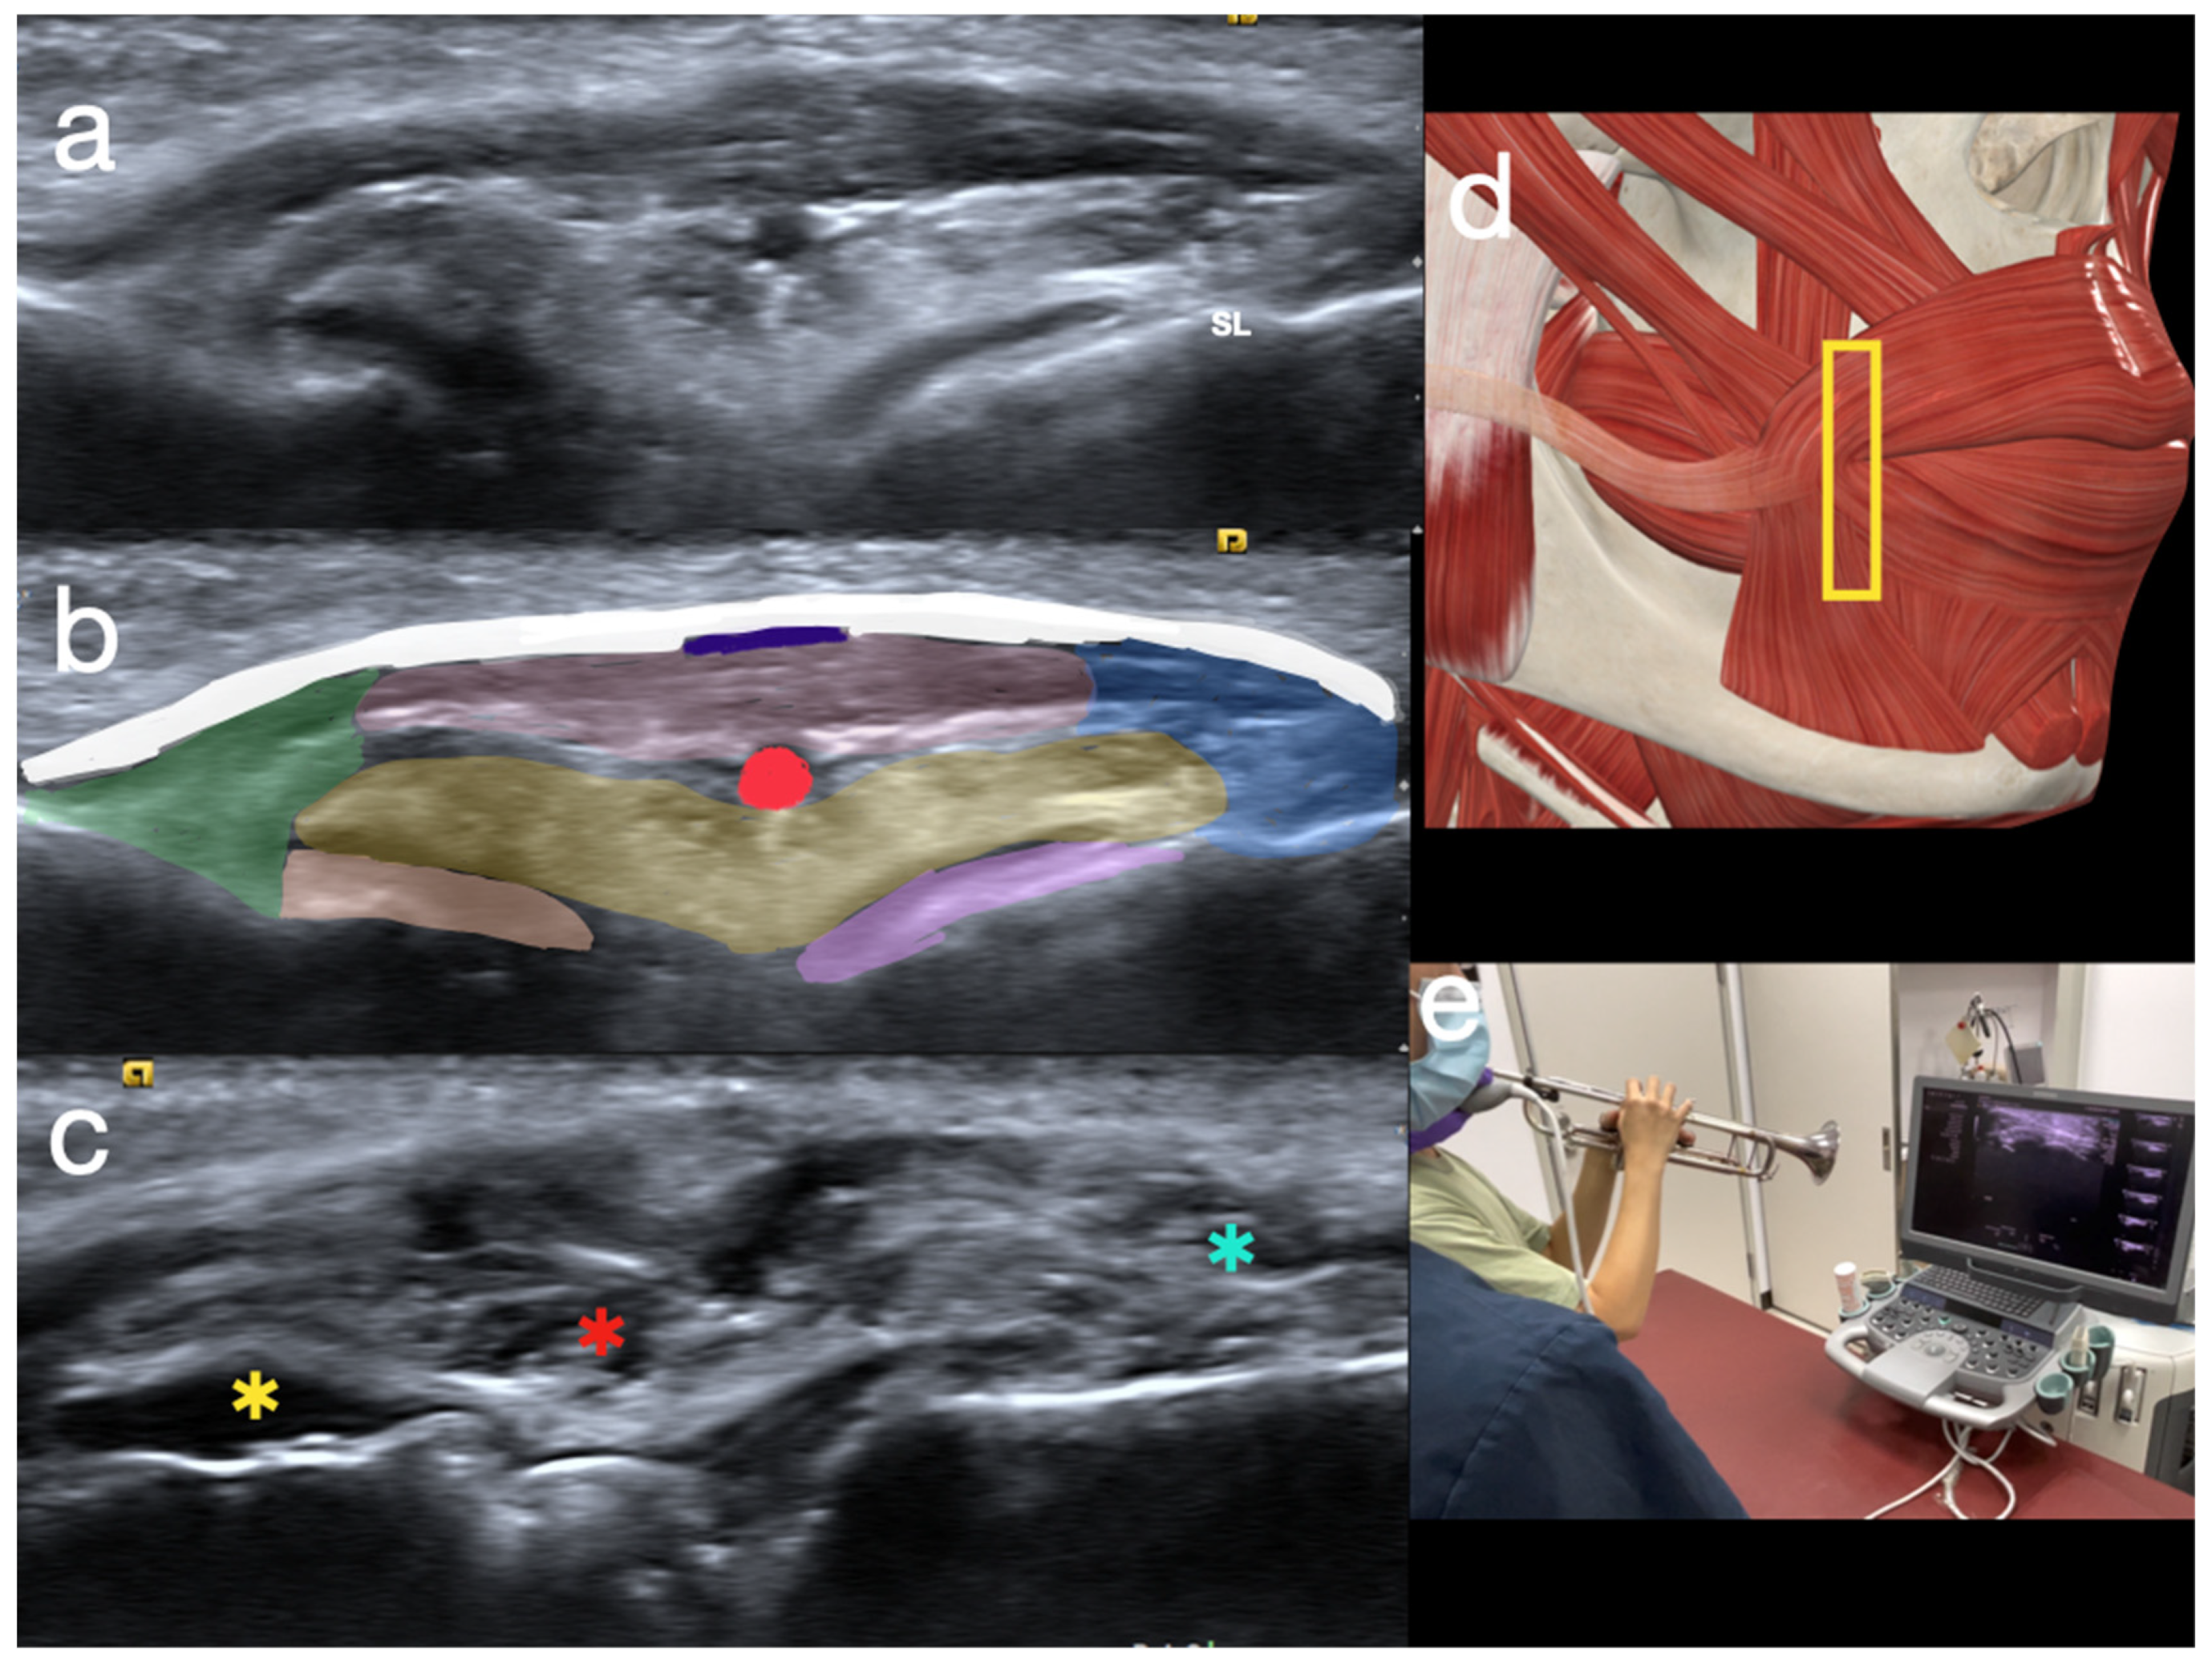

2.1. Sonoanatomy of Peri-Oral Musculature and Fascia System Concerning Embouchure

2.2. Scanning Protocol for the Embouchure in Wind Players